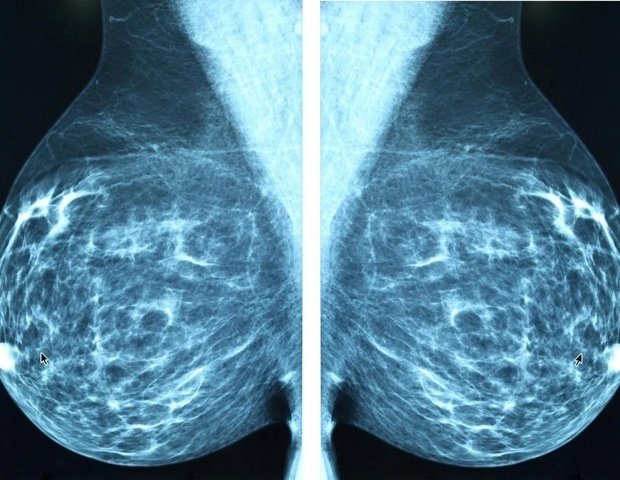

Some breast cancer treatments, including anthracycline chemotherapy and drugs that target HER2, such as Herceptin (trastuzumab), are known to stress the heart in some patients. For years, doctors have monitored patients during treatment to detect early signs of heart dysfunction.

In the editorial, Dr. Ganz and Dr. Yang evaluated a study that introduced a new tool to help identify which breast cancer survivors face the highest odds of developing heart failure or cardiomyopathy in the decade after treatment. The team created a risk calculator using real-world clinical data from more than 26,000 breast cancer patients in an integrated healthcare system in Southern California.